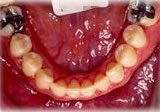

反対咬合(受け口)症例

初診時年齢24歳6ヶ月。前歯部反対咬合を主訴に来院。

骨格性反対咬合と診断し、外科的処置を併用して治療。

下顎 下顎 下顎